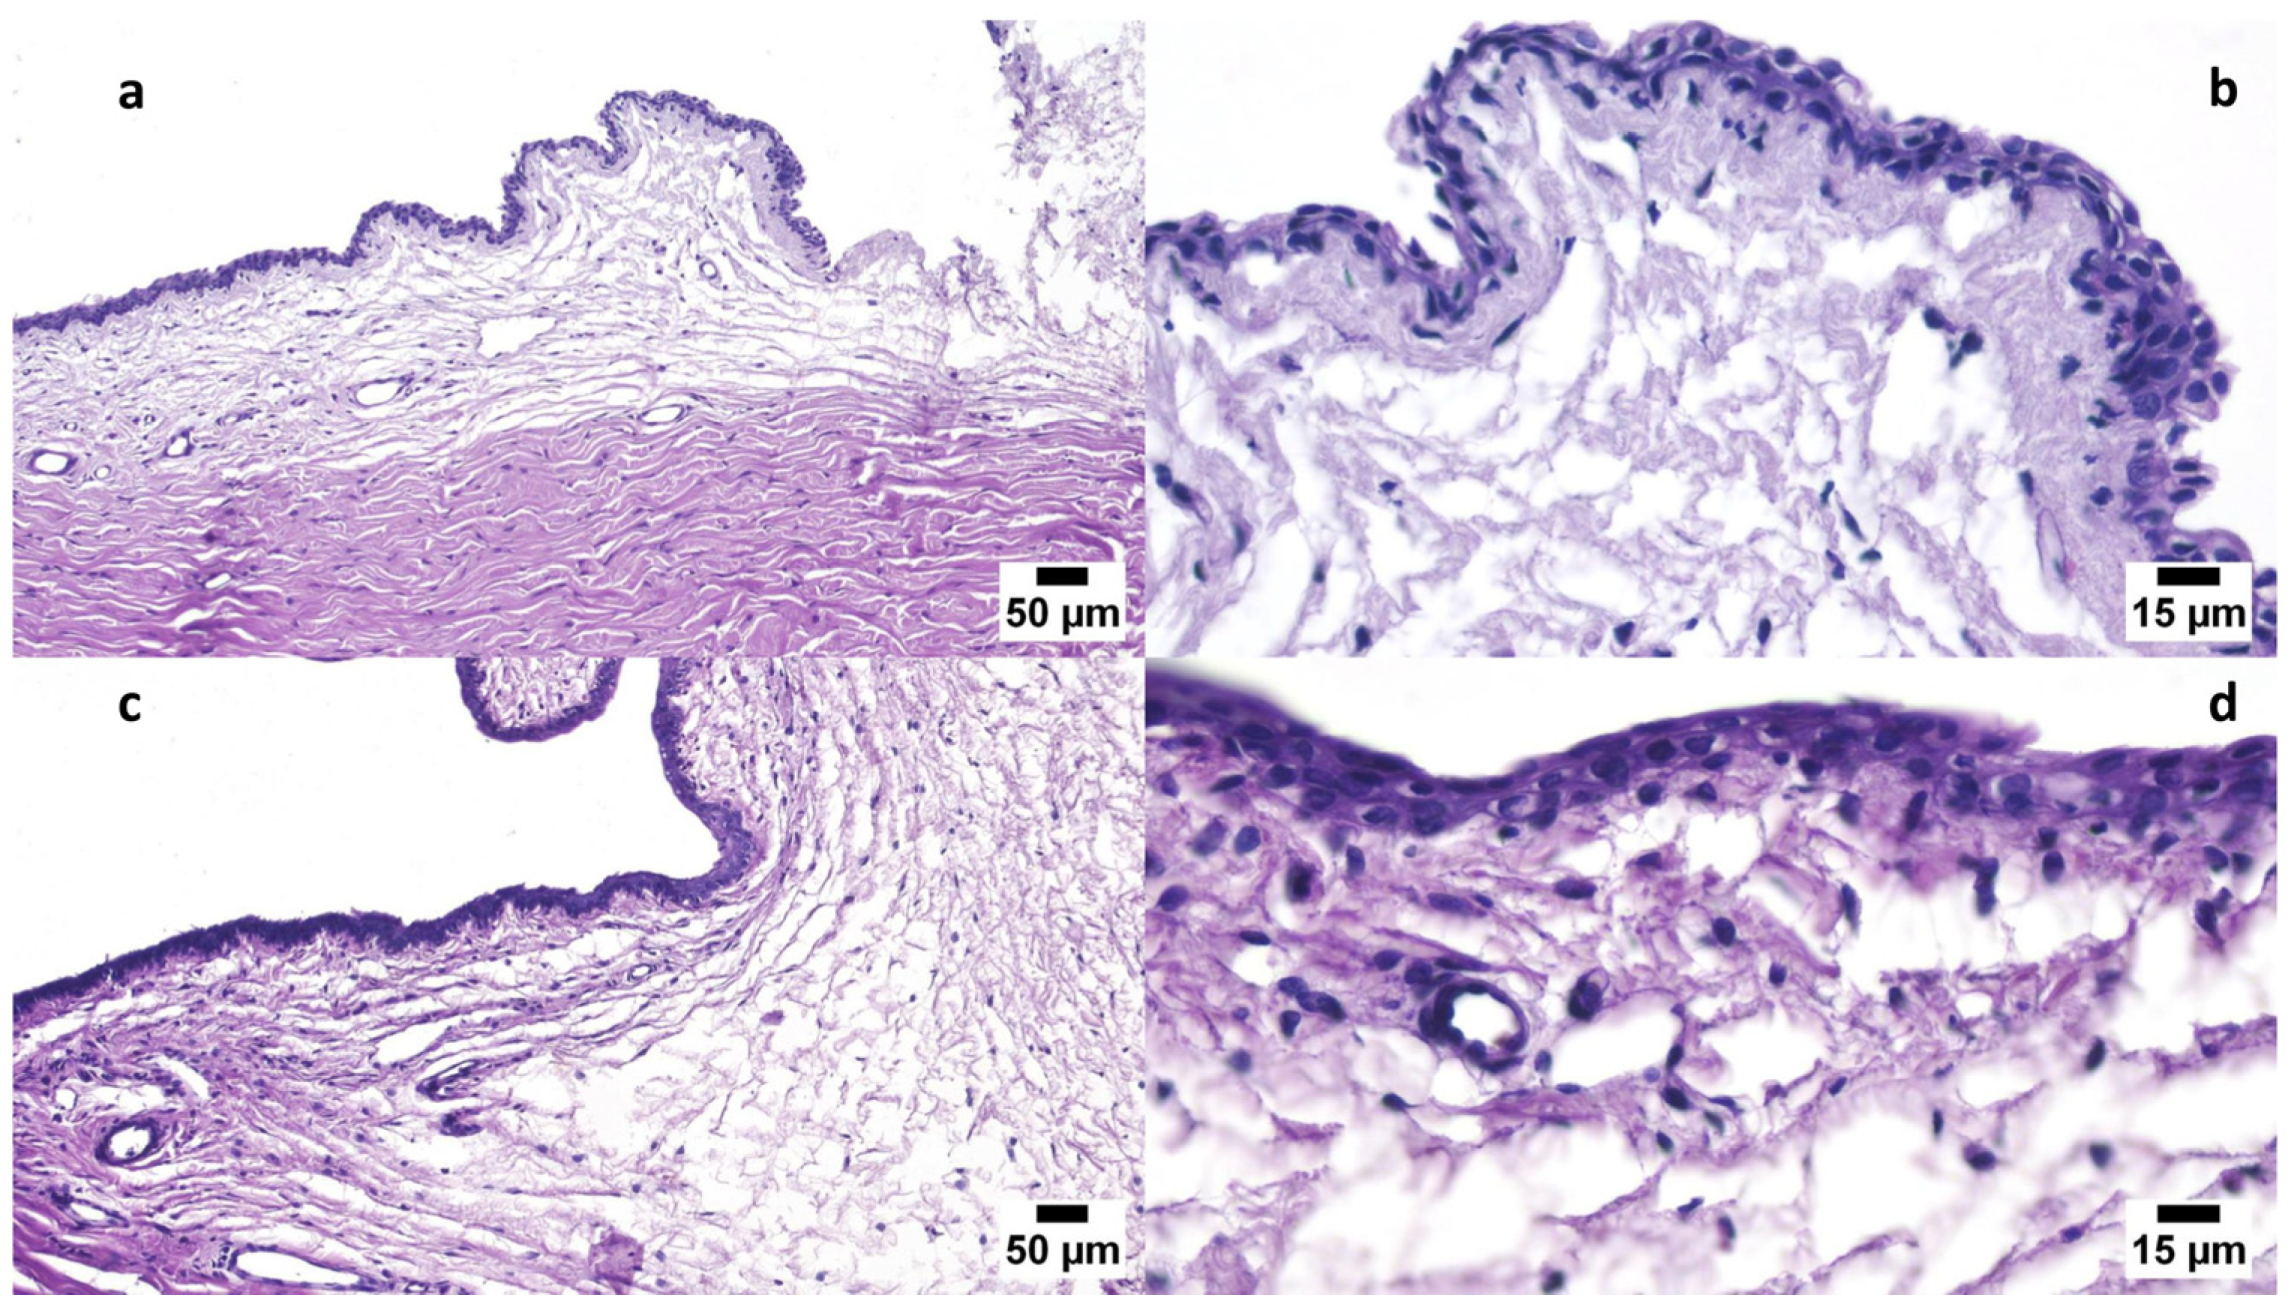

3.6.1. Draize Test

- El-Emam, G.A.; Girgis, G.N.S.; Hamed, M.F.; El-Azeem Soliman, O.A.; Abd El Gawad, A.E.G.H. Formulation and Pathohistological Study of Mizolastine–Solid Lipid Nanoparticles–Loaded Ocular Hydrogels. Int. J. Nanomed. 2021, 16, 7775–7799. [Google Scholar] [CrossRef] [PubMed]